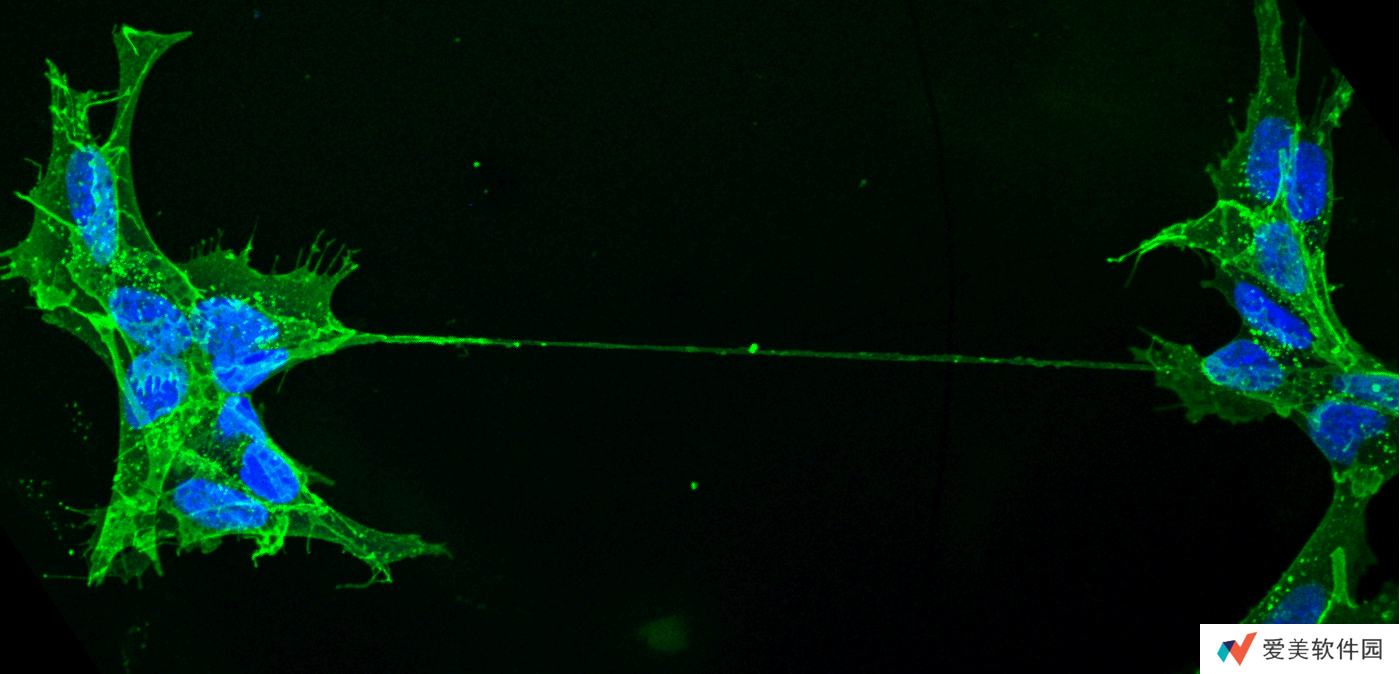

此前,研究人员已在活体外实验中观察到隧道纳米管。在新研究中,巴斯德研究所团队选用易于观察的透明斑马鱼胚胎,对胚胎细胞进行荧光标记,并借助活显微镜细胞成像技术追踪观察。

自 2003 年德国与瑞士团队首次在体外实验中观察到 TNT 以来,科学界对这一结构的生物学意义长期存在争议。为突破研究瓶颈,巴斯德研究所膜运输与发病机制单元负责人 Chiara Zurzolo 教授率领由 15 名青年科学家组成的国际团队,选用具有透明特性的斑马鱼胚胎作为研究对象,通过荧光标记技术与活体显微成像技术(包括 3D 活细胞荧光显微镜、超分辨率显微镜及冷冻电镜),首次捕捉到活体生物中 TNT 的动态形成过程。

研究发现,斑马鱼胚胎细胞间延伸出的细长中空管状结构确认为 TNT,并观察到线粒体通过该通道在细胞间转移的现象。“这不仅证实 TNT 在活体内的存在,更表明其对胚胎健康发育具有重要作用。”Zurzolo 强调。此前,科学界仅在体外实验中观察到此类现象。